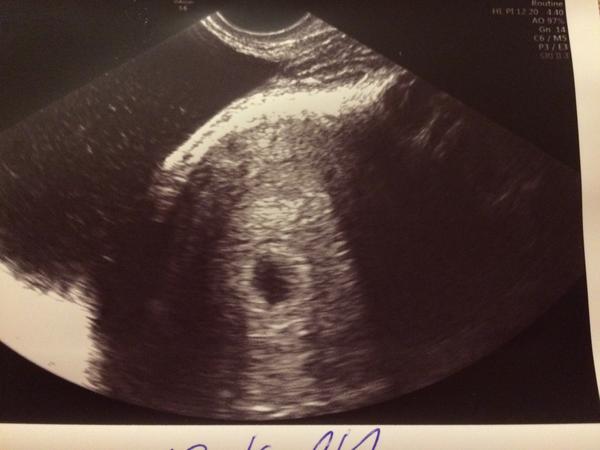

Ahojte, tak my už mame za sebou aj prvý ultrazvuk, na akciu srdiečka si však ešte počkáme🙂 musela som ísť k dr skor, pretože som mala zvýšenú teplotu (37,6) a veľmi ma bolel žalúdok, tak pre istotu a všetko je ako ma byt. Mám aj takú rozmazanu fotku (robila ju taká staršia dr ktorá ordinuje u mojej dr raz týždenne a s ultrazvukom jej to evidentne nejde😀)